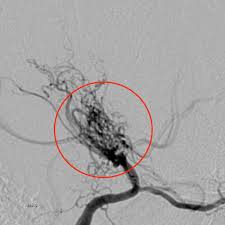

모야모야병은 뇌 기저부에 있는 주요 혈관이 점차 좁아지면서 뇌로 가는 혈류량이 줄어드는 질환입니다. 혈류가 부족해지면 뇌는 새로 가늘고 약한 혈관을 만들어 혈류를 보완하려고 하는데, 이 혈관들이 모여 있는 모습이 연기처럼 보여 ‘모야모야’라는 이름이 붙었습니다.

가느다란 보조 혈관이 쉽게 파열되기 때문에 즉각적인 응급 치료가 필요합니다.